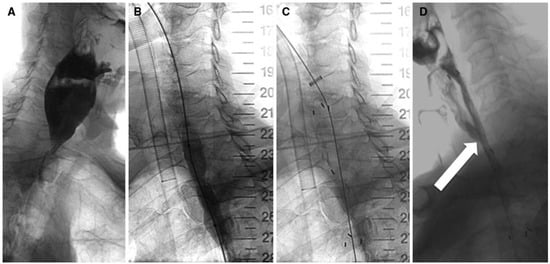

- Černá, M.; Köcher, M.; Válek, V.; Aujeský, R.; Neoral, Č.; Andrašina, T.; Pánek, J.; Mahathmakanthi, S. Covered biodegradable stent: New therapeutic option for the management of esophageal perforation or anastomotic leak. Cardiovasc. Interv. Radiol. 2011, 34, 1267–1271. [Google Scholar] [CrossRef] [PubMed]